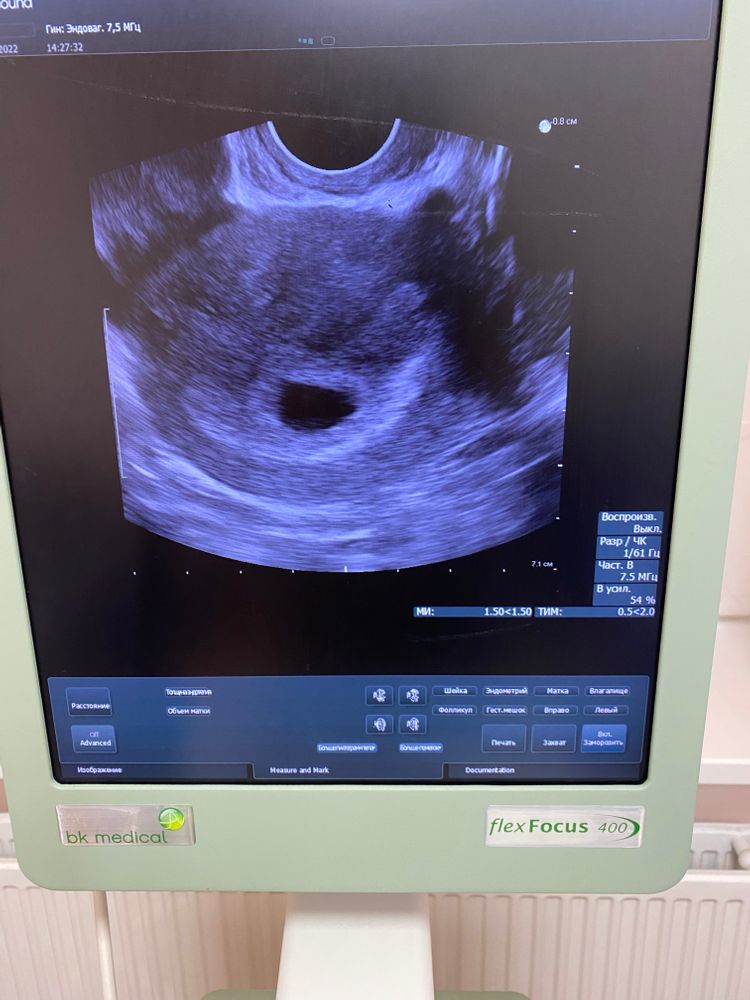

сходила вчера на первое узи … и незнаю что думать 🤔 всё как то неопределенно!!!

Жм не увидел пя вроде как тоже ссылаясь на то что срок маленький-велели через 2нед снова прийти на узи ….но я чёт так переживаю😬 у кого то может была подобная ситуация ? Расскажите 🙏

Так ПЯ увидели у вас в результатах.

у вас все понятно написано,через две недели прийдете, посмотрят на наличие ЖМ и эмбриона